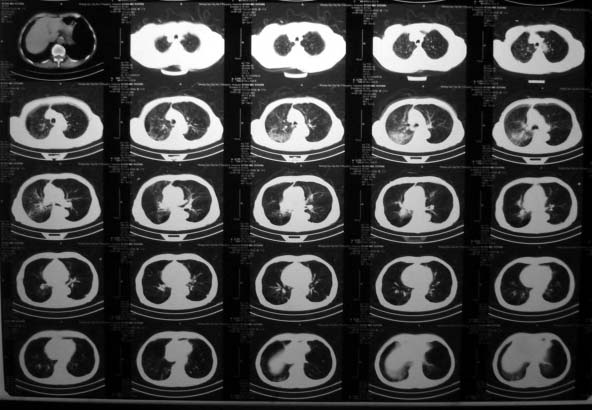

标题: CT10435:男,77岁,肺癌吗?

男,77岁,血丝痰一月,消炎治疗后血痰消失。

一直消炎治疗一月 。

考虑右肺下叶炎症可能性大,建议治疗后复查。另外图像太小了,让我们炼火眼金镜呀!

平片太黑,ct图片太小,考虑右肺下叶炎症,建议治疗后复查。

考虑两肺结核可能性大,建议排除支气管肺泡癌

患者年龄偏大,有咯血症状,首先考虑右肺阻塞性肺炎,图象太小气管狭窄看不太清,建议纤支镜检查.

以浸润型肺结核合并感染可能性大。

考虑右肺下叶炎症可能性大,结核不能排除,建议治疗后复查或结合ppd检查。

这个病例我考虑是慢性支气管炎合并右肺细菌性感染。老年人建议作血糖检测。

患者血糖正常,只是治疗中(在基层)出现电解质紊乱(低钠、低氯)

经补电解质及支持治疗患者好转出院。

右肺炎症,结核不完全除外,建议抗炎治疗后复查。